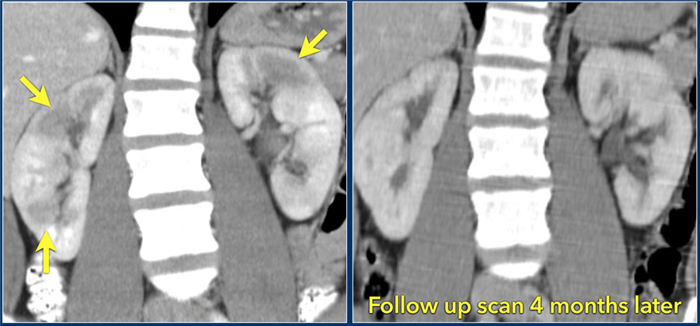

При визуализации картина при пиелонефрите или абсцессе почки схожа с картиной при опухоли, поэтому результаты анамнеза, осмотра и других клинических данных помогают радиологу в постановке правильного диагноза. В представленном случае визуализируются гиподенсные образования в обоих почках. Если диагноз базировать только, исходя из данных изображения, то напрашивается следующий дифференциальный ряд: пиелонефрит, лимфома или метастаз.

Данный пациент поступил с жалобами на боль в боку и с анамнезом воспалительного поражения мочевыводящих путей, также у пациента отрицательный онкологический анамнез, поэтому диагноз — пиелонефрит.

На КТ спустя 4 месяца визуализируются нормальные почки. На первом изображении патологическая картина обусловлена мультифокальным пиелонефритом.